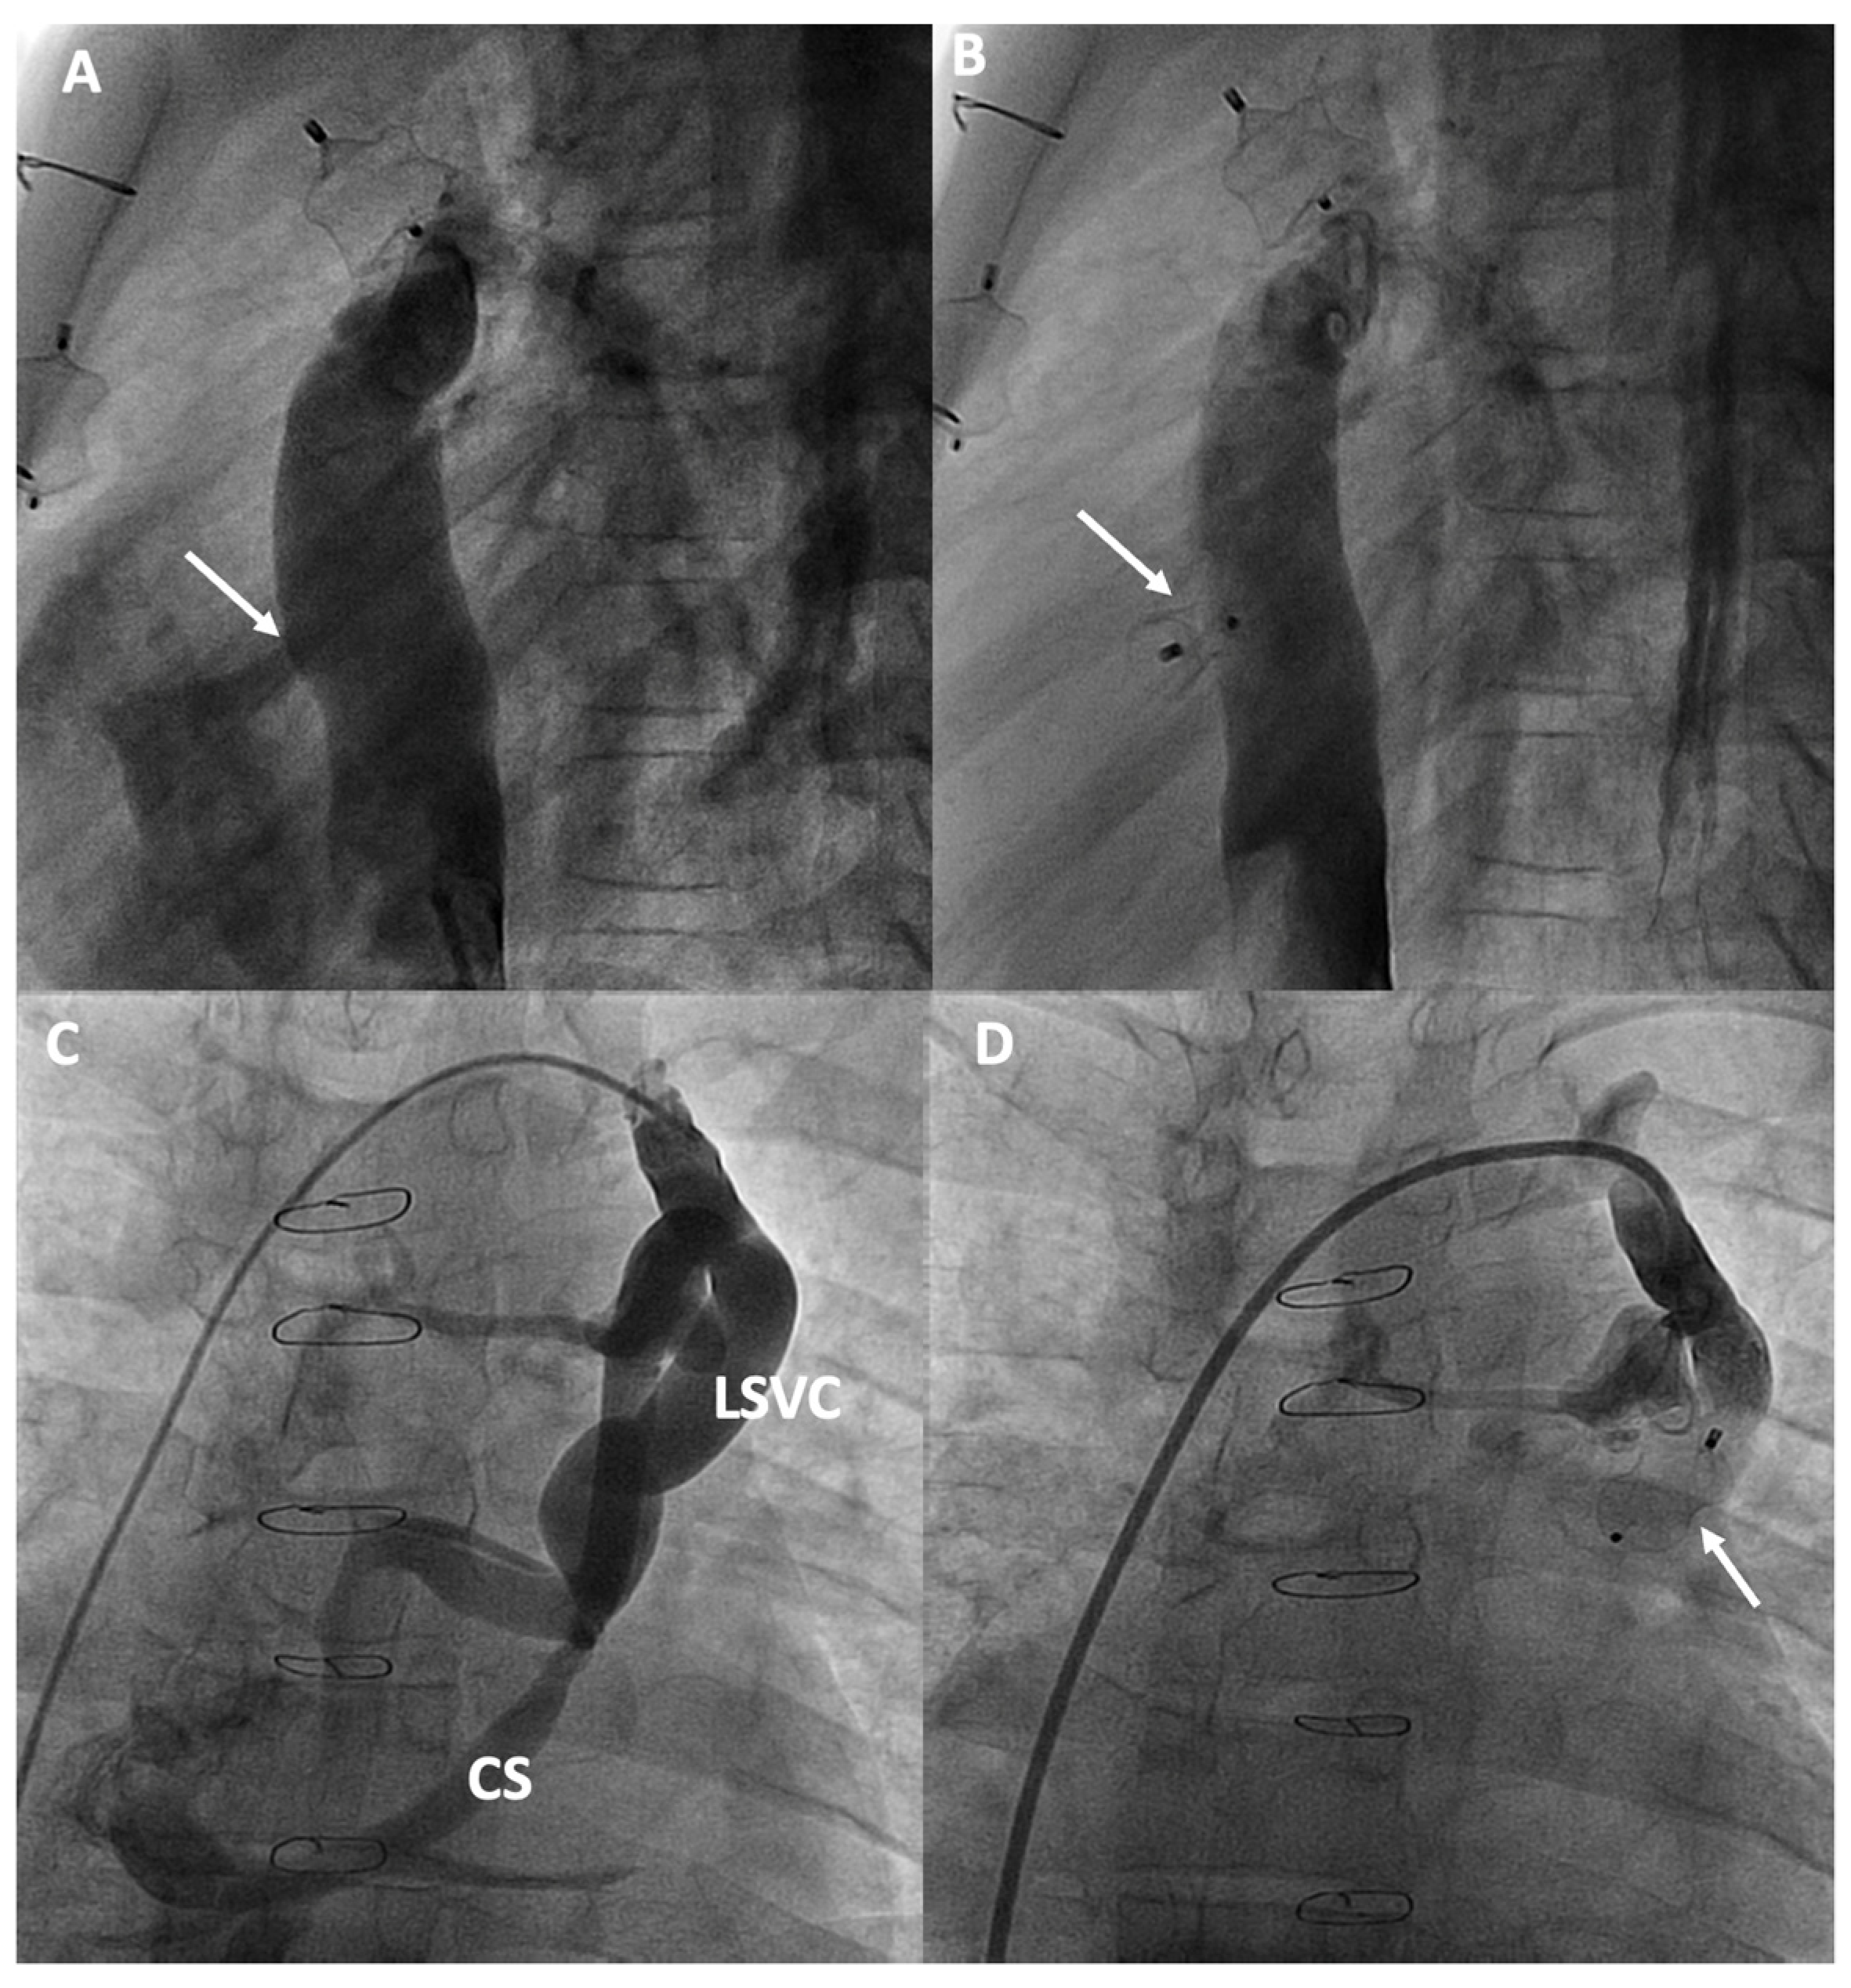

3.4. Management of Lymphatic Circulation

| Lymphatic Circulation | Selective lymphatic embolization and percutaneous thoracic duct decompression can be used to manage lymphatic disorders. |